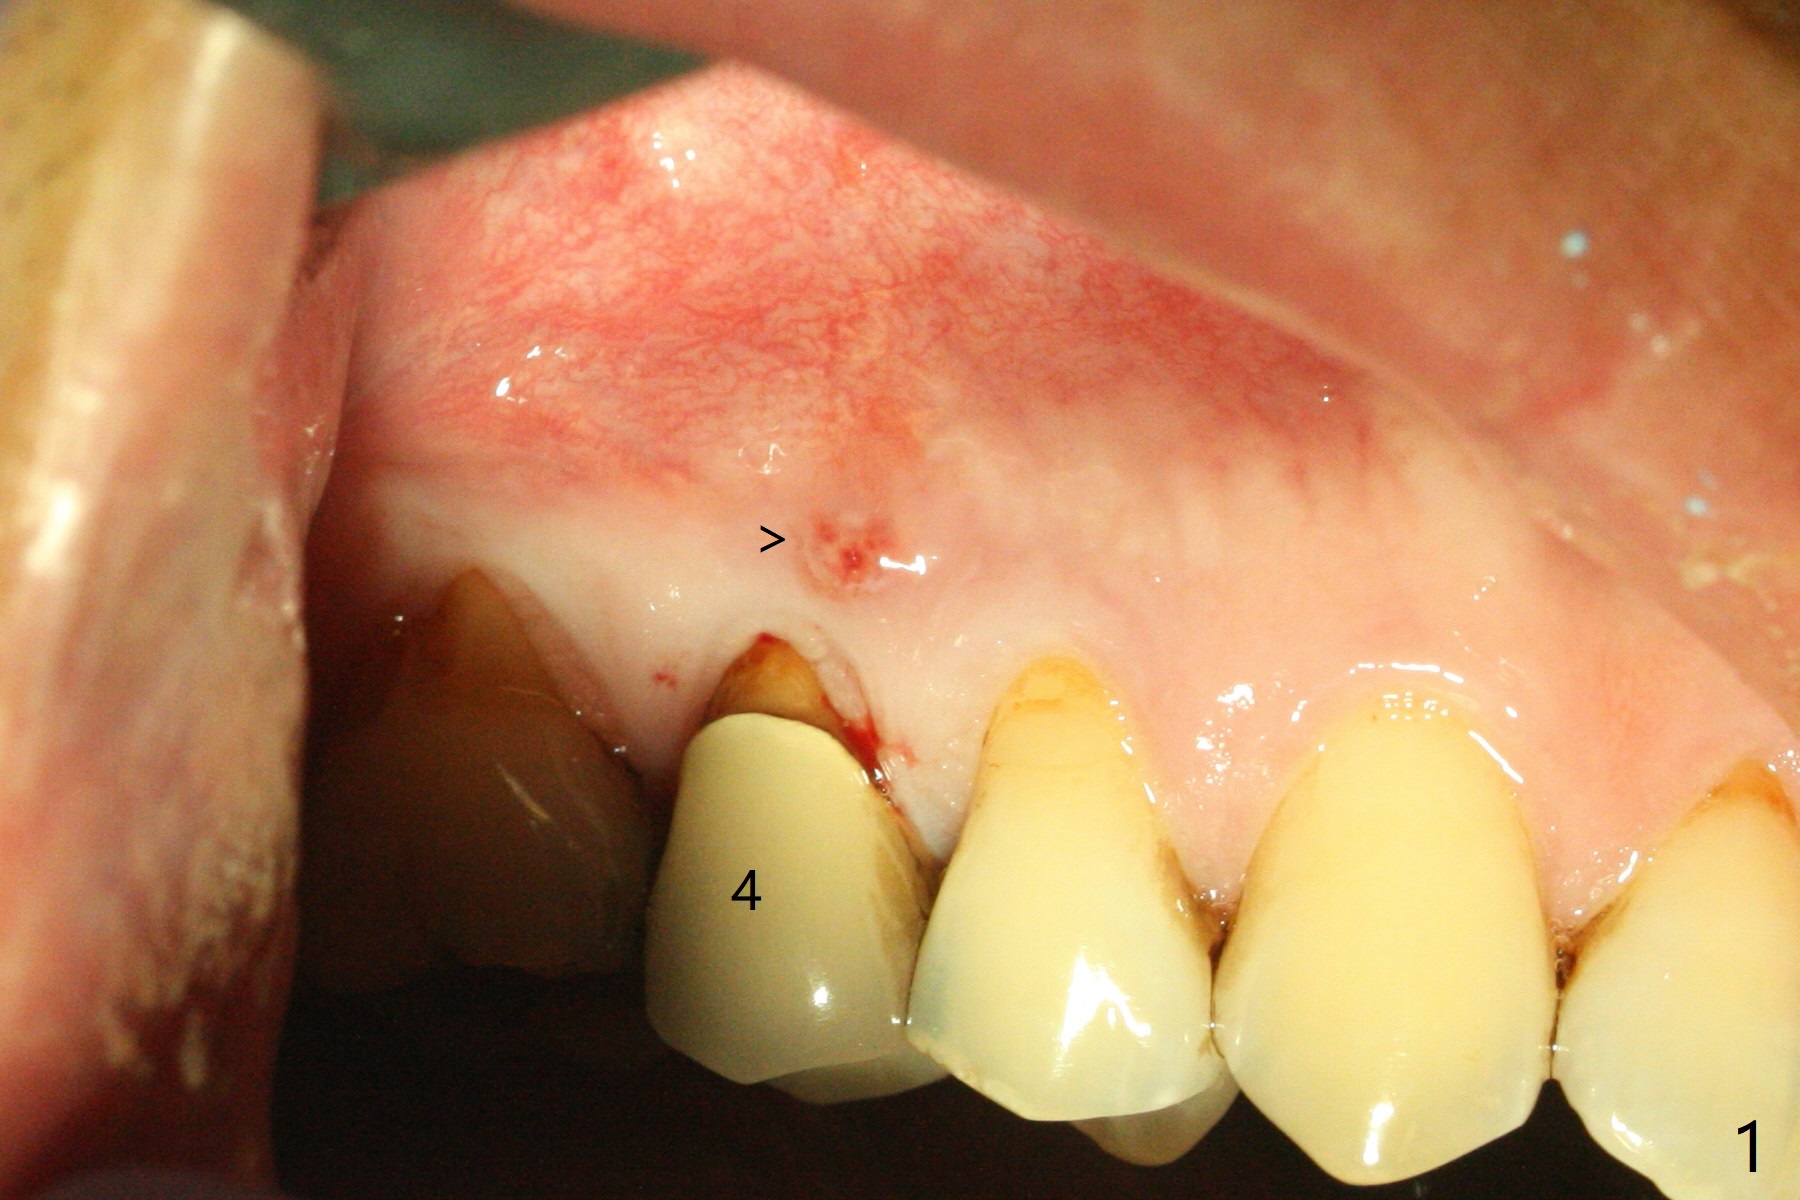

The 48-year-old man agrees to extract the tooth #4 with buccal and palatal fistulae (Fig.1,2 >) and large PARL (Fig.3 *) because of purulent discharge. The large post (Fig.3 P) is most likely associated with a longitudinal fracture. The latter is not noted until postop (Fig.4 <). Intraop finding is large amount of granulation tissue removed from the mesial apical region (Fig.3,5 *). With 10.5 mm offset, Sinus Approach Drill (19 mm) is estimated too short for sinus lift after 3x8.5 mm drill. Without careful repeated check, 2.2x10 and 2.2x11.5 mm drills are used. The sinus floor is perforated, but the membrane seems to be intact. The perforation is too small to insert PRF, but alright for allograft. Then nose blowing test shows that the sinus membrane is perforated, which seems to be repaired after placement of 2 pieces of PRF membrane, followed by another round of allograft (Fig.5 G), which is lifted by a 4x10 mm IS dummy implant. Before placement of a 4.5x11.5 mm final UF implant, allograft is placed in the 3 defective bony areas mentioned above, including the apical mesial one (Fig.6 *). But the final UF implant seems too short with non-satisfactory torque. The latter appears to be solved with the increased length of the implant (Fig.7). The gingiva around the provisional (P) is healthy without fistulae buccal (Fig.8) or palatal 17 days postop (Fig.9). A new abutment with 1 mm longer cuff is seated completely 5.5 months postop (Fig.10 < (no gap), as compared to Fig.7). The lower portion of the mesial defect seems to have been repaired (Fig.11 arrow, as compared to Fig.7). The bone in the sinus seems stable 1.5 years postop (Fig.12). There is no crestal bone loss 4 months post cementation (Fig.13). Return to Upper Premolar Immediate Implant, Trajectory II Xin Wei, DDS, PhD, MS 1st edition 09/27/2019, last revision 04/12/2021